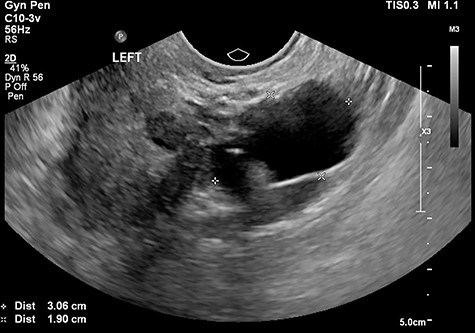

The tertiary level gynaecological ultrasound demonstrated a right adnexal serpiginous structure with a lumen and incomplete septae and a left adnexal cystic structure (Figs 1 and 2). The ultrasonographic features were consistent with those of hydrosalpinges [12]. The Ca125 remained negative. In view of the ultrasound diagnosis of hydrosalpinges and the patient’s post-menopausal status, a laparoscopic BSO was recommended and the patient subsequently consented.

The tertiary ultrasound of the left adnexa demonstrating a 30 mm × 19 mm × 27 mm cystic structure with incomplete septae in keeping with a possible hydrosalpinx.